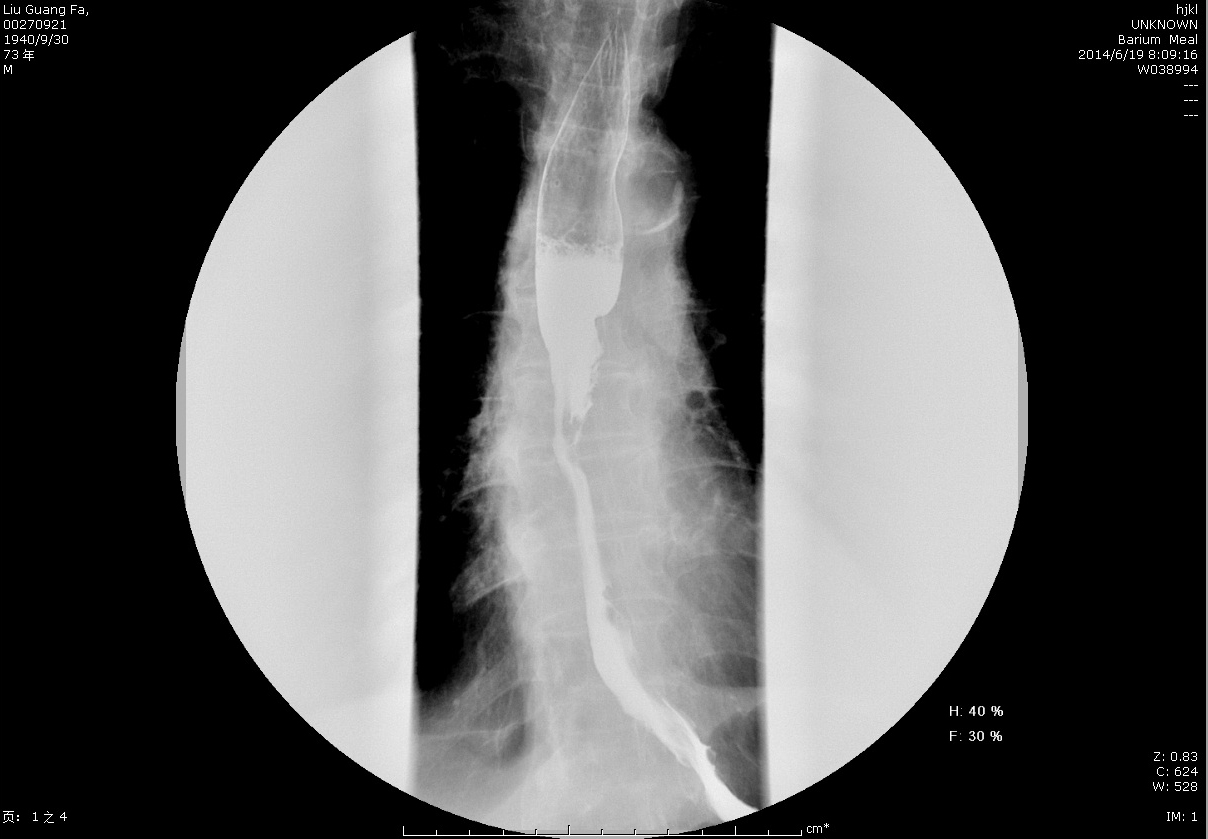

圖3+術(shù)前鋇餐